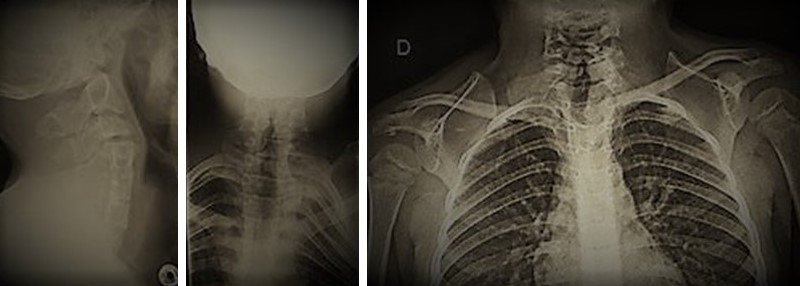

Klippel-Feil Syndrome and Sprengel Deformity